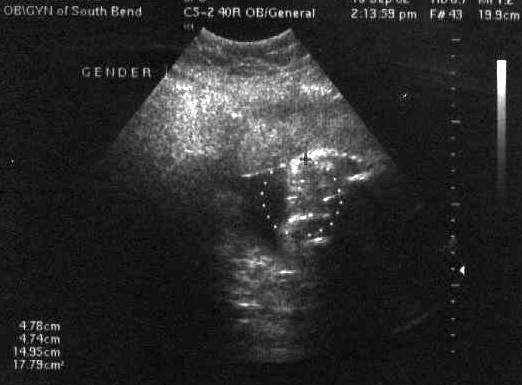

| Well, we finally got our long-awaited ultrasound to determine the sex. Unfortunately, Duckie refused to cooperate! Read all about it here in my journal entry from July 30. However, all was well and we got this amazing picture of the baby. The eye sockets, nose and teeth are all clearly visible. (July 30, 2002 - 23 weeks, 1 day) |